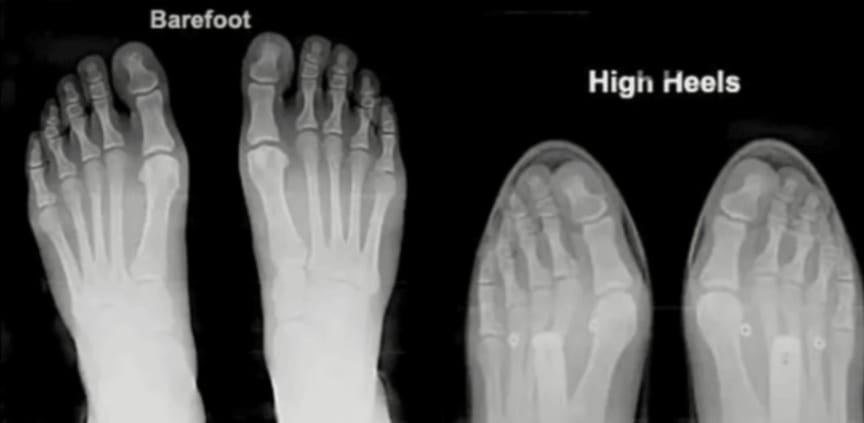

When we compare the feet of people who habitually walk barefoot to those who wear modern shoes, the difference is striking. Barefoot populations typically have wide, strong feet with toes that spread naturally. In contrast, modern shoes squeeze the toes together, weakening the arch and forcing the skeleton out of its natural alignment.

Do your feet look like this?

Look at this X-ray comparison: